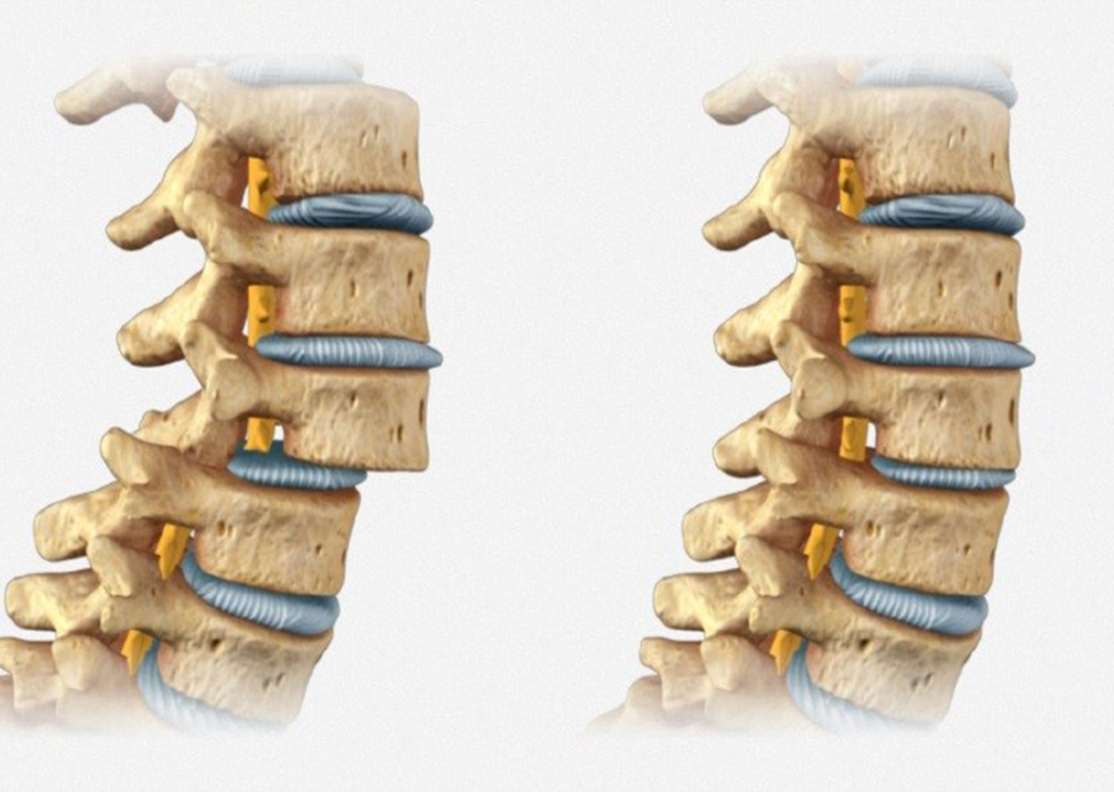

Hernia del núcleo pulposo

La hernia del núcleo pulposo (HNP), es la protrusión del material gelatinoso central de un disco intervertebral a través de una fisura en el anillo fibroso que lo rodea. El anillo puede romperse completamente con salida de material discal, o puede permanecer parcialmente intacto y dar lugar a una protrusión discal que puede comprimir el nervio, generando dolor y parestesias.